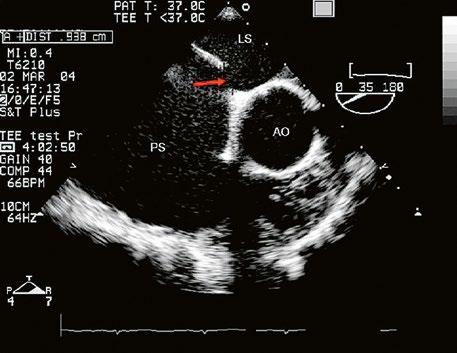

Obr. 45.36 Valvární pulmonální stenóza, doming cípů, jemné cípy, srůst komisur (TEE, longitudinální projekce) AP – kmen plicnice, PK – pravá komora, PS – pravá síň

Obr. 45.37 Valvární stenóza plicnice, jemná chlopeň, doming cípů, TEE, longitudinální projekce, pacient s transpozičním postavením velkých tepen, aorta (AO) je vepředu, plicnice (AP) vzadu